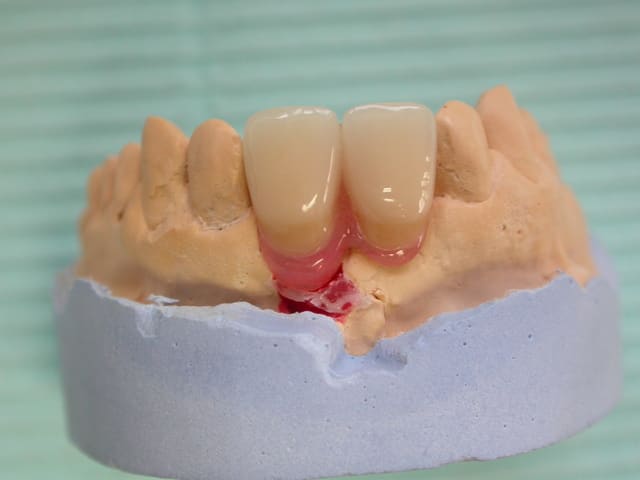

Comme je n'ai pas pu trouver la marque de l'implant, j'ai du me débrouiller autrement pour dépanner ce patient( à la cmu).

Voilà quelques photos de l'étape provisoire et du definitif avec un ancrage dans l'impant et des ailettes palatines.

Un grand merci à mon prothésiste.